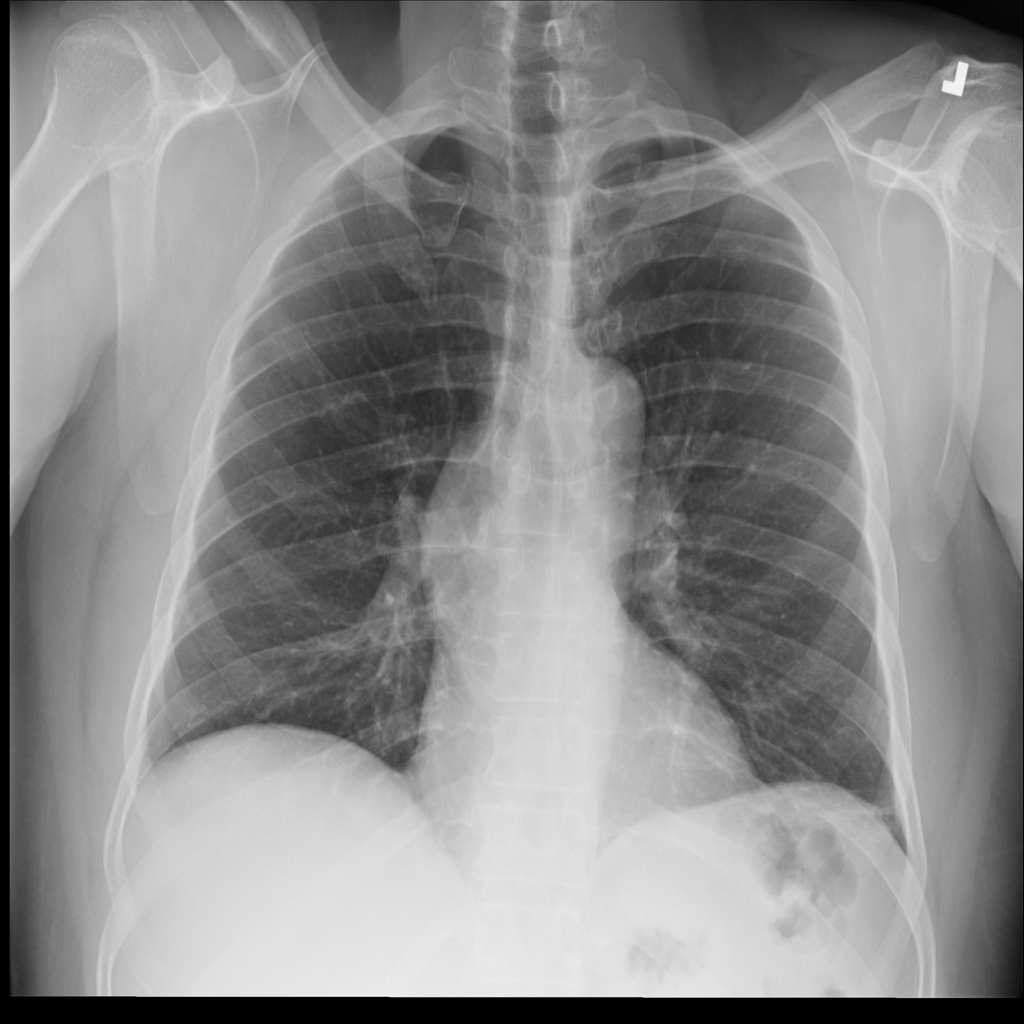

PAT-DB80 · IMG-001Atelectasis

PAT-DB80 · IMG-001

PA